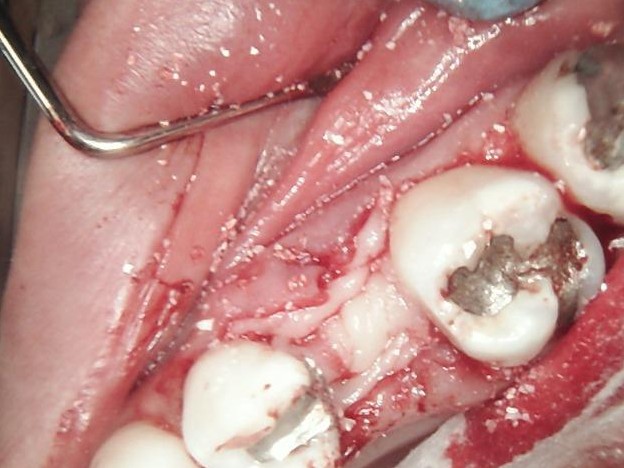

SURGERY

The failed implant was atraumatically removed, followed by thorough debridement of the surgical site.

Bone graft material was placed to restore adequate bone volume and support future implant placement.

A new implant was inserted in a prosthetically driven position, ensuring primary stability.

Surgical site was sutured to allow uneventful healing.